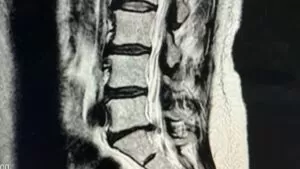

長年の職業病による腰痛。腰を屈める時間が多く腰を伸ばせなくなり脚に痺れがある状態で来院されました。

痺れの原因はMRIで顕著。治療後は腰は真っすぐになり足の痺れも軽減しますが、仕事中屈む姿勢が多く戻り気味でした。